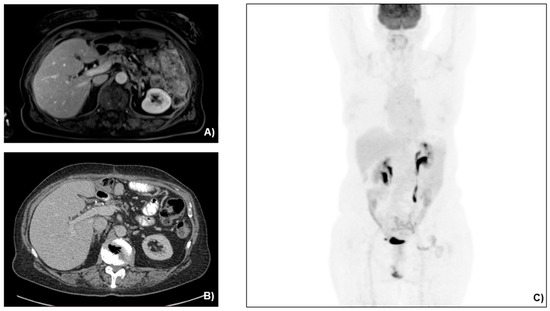

A 69-year-old female, with an unremarkable medical history, underwent an upper-GI endoscopy for progressive dysphagia for solid and liquids. A brittle ulcerous lesion with partial occlusion and signs of recent hemorrhage was detected at the EGJ with expansion to the lesser curvature of the gastric cardia, classified as a Siewert III tumor (Figure 1). The histopathological analysis of the endoscopic biopsies revealed a poorly differentiated invasive adenocarcinoma with HER-2 expression to be negative. The clinical staging included computed tomography (CT) (Figure 2) followed by a staging laparoscopy. Imaging demonstrated a locally advanced tumor (cT4) with a bulky locoregional lymph node packet (cN+) and three liver lesions consistent with hepatic metastases. In front of a possible oligometastatic state of disease, a staging laparoscopy took place to exclude peritoneal seeding and facilitate the application of a percutaneous feeding tube. During laparoscopy, macroscopic peritoneal seeding was excluded, while both the bulky lymph nodes at the lesser curvature and the largest liver metastasis at the left liver lobe could be visually detected (Figure 3). Remarkably, these tumorous lesions demonstrated a soft consistency in palpation with the laparoscopic forceps, which was not expected, as metastatic lesions from adenocarcinoma primary are anticipated to have a solid and hard texture. Therefore, a lymph node biopsy at the lesser curvature of the stomach was contacted in order to exclude different histopathology. The peritoneal cytology after collection of peritoneal washings proved to be negative.

Figure 2. (A,B) Initial abdominal computed tomography in coronal and (C,D) axial views, depicting the gastric lesion and liver metastatic lesions (red arrows).